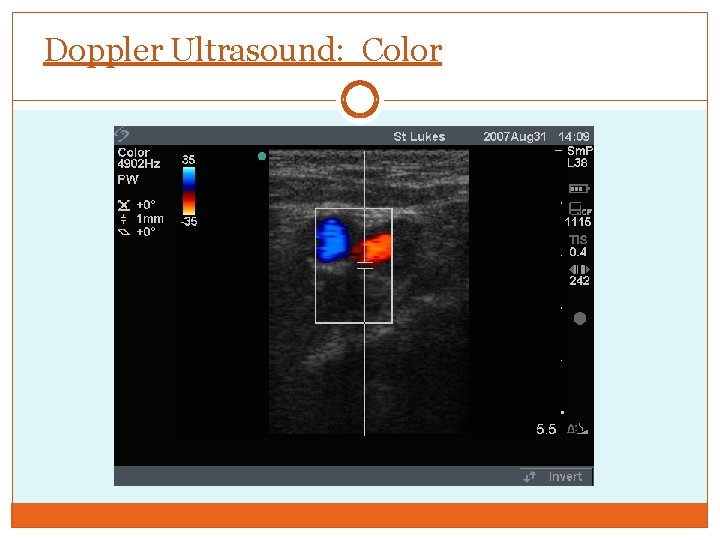

Doppler Ultrasound: Color